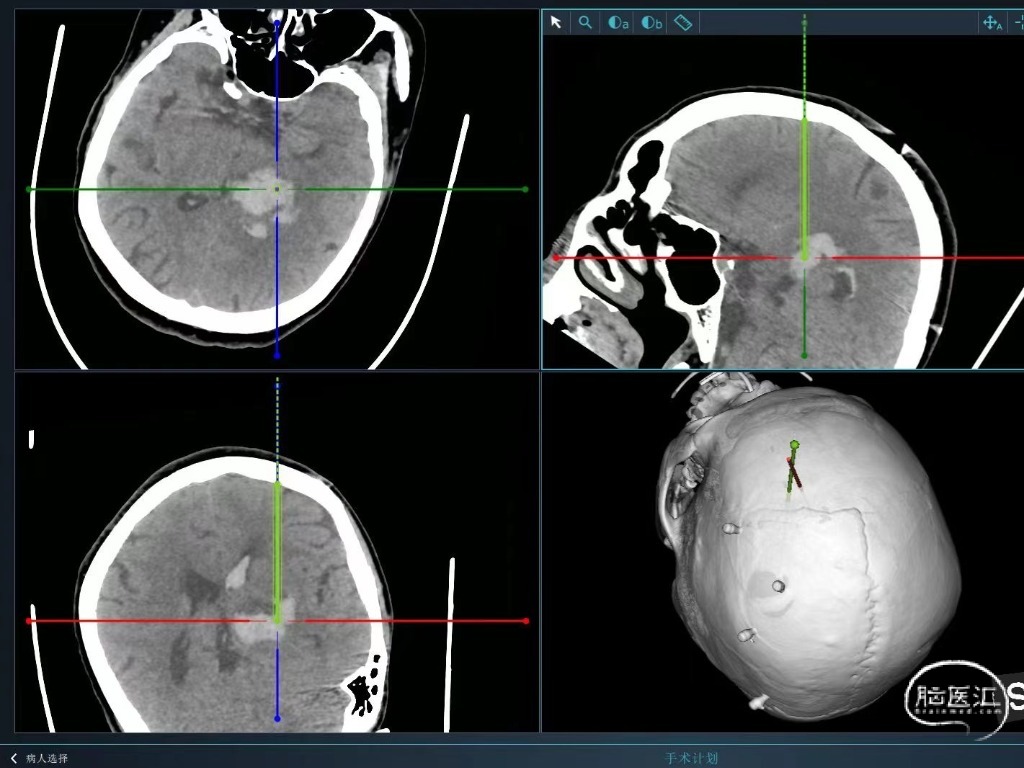

既往史:患者于入院前3小时工作时无明显原因及诱因出现右侧肢体无力,伴短暂意识丧失,随后患者呈嗜睡状,无恶心、呕吐,经短暂休息后,未见好转,经120送入我院急诊,急诊行头颅CT示:左侧丘脑出血破入脑室,出血量约为20ml。

辅助检查:头颅CT(我院):右侧丘脑出血破入脑室,出血量约20ml。

术中

一孔两管